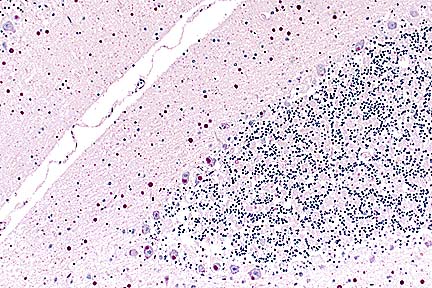

Non suppurative meningoencephalitis in an Appaloosa gelding infected with equine lentivirus (HE, 100X, 76K)

Contributor's Diagnosis and Comments: Severe nonsuppurative meningoencephalitis and choroid-plexitis with microgliosis. Lentivirus of equine infections anemia (EIA).

This case represents a classic presentation of the neural form of EIA. In the contributors experience, less than 2% of Coggin's positive horses have evidence of CNS involvement. This horse had typical gross lesions of recrudescing EIA. The farm of origin has had problems in the past with EIA and this case caused a quarantine to be placed on the farm.

The CNS lesion typically has an "inside out" pattern, whereby the inflammation is severe around the ventricular system. In this horse, that was best seen in the spinal cord. This horse tested negative for sarcocystosis, neosporsosis, VEE and EEE.

AFIP Diagnosis: Cerebellum, brain stem, midbrain, and choroid plexus: Choriomeningoencephalitis, nonsuppurative, multifocal, moderate, Appaloosa, equine.